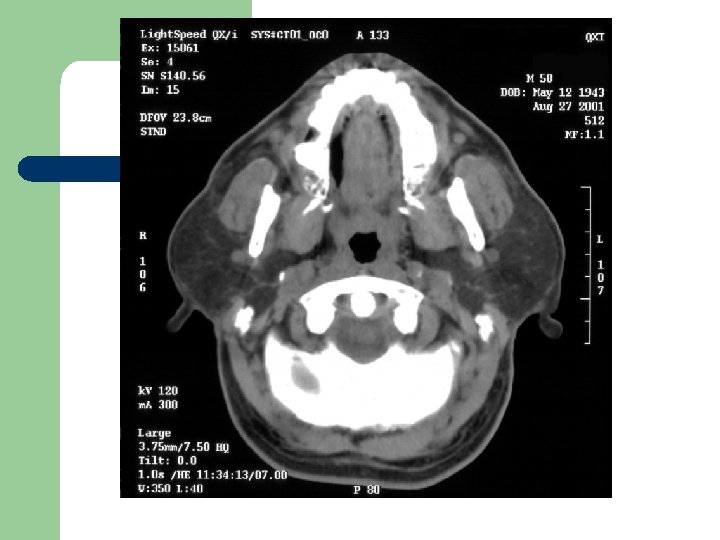

Radiological Evaluation l CT Scan and MRI: To determine the extension of the disease.